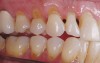

Fig. 10 Non-carious cervical lesions are evident in both arches.

Figure 10  Non-carious cervical lesions are evident in both arches.

Figure 10